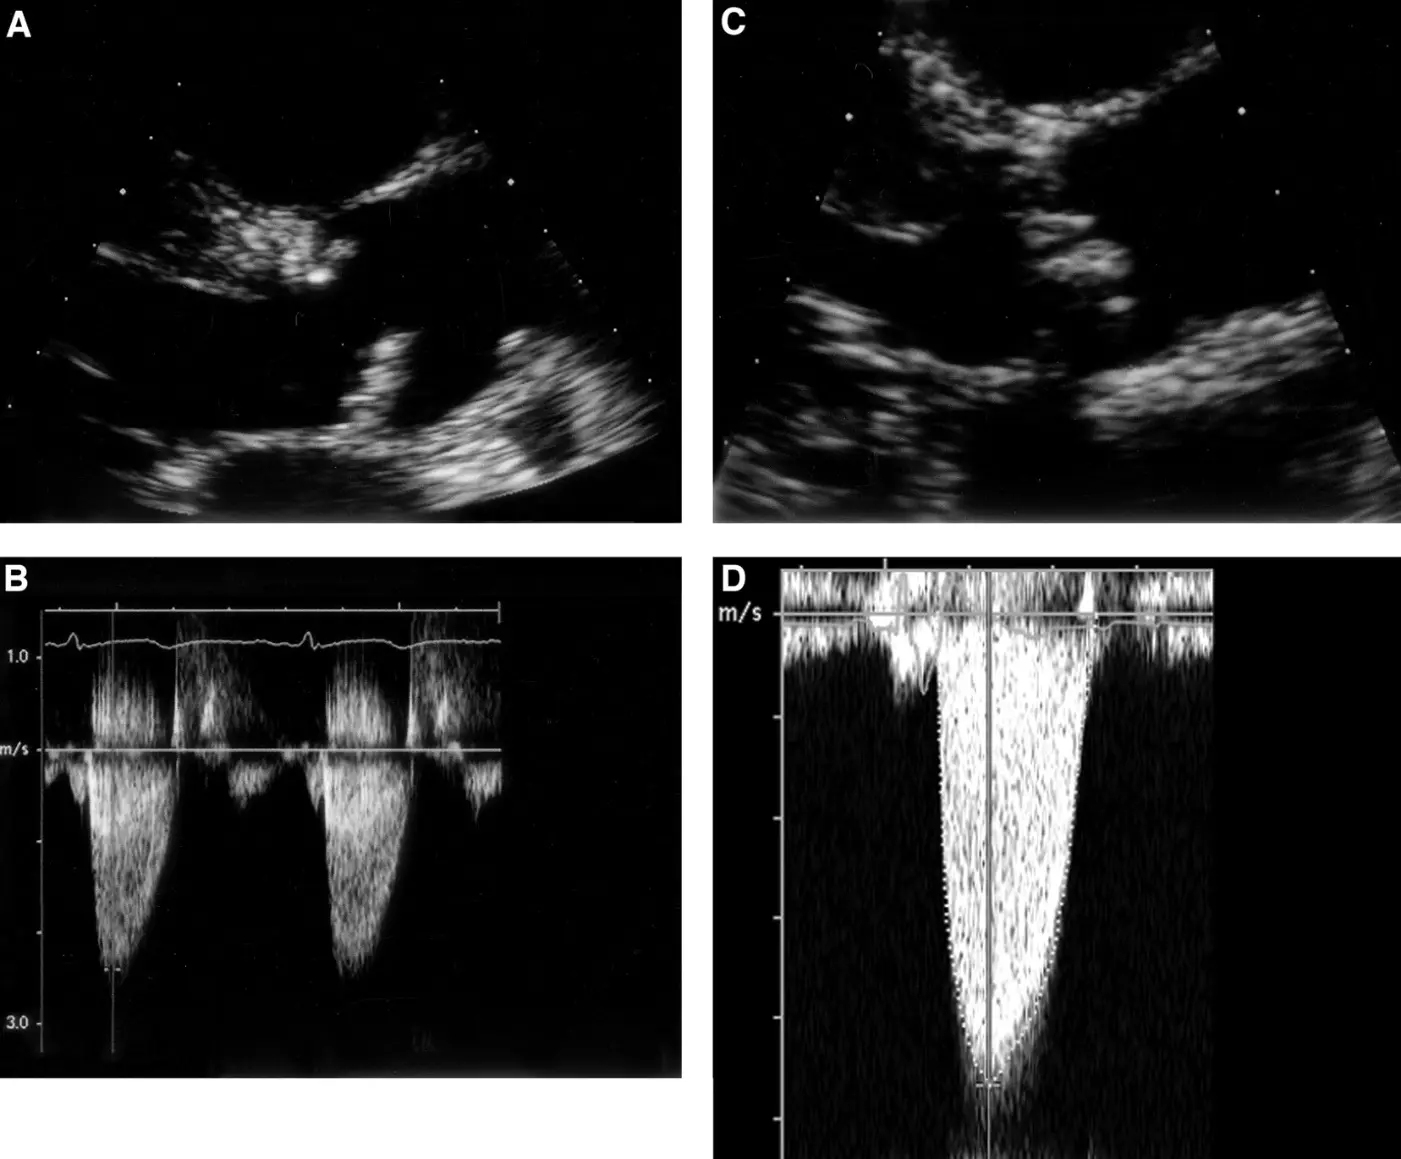

Once the valve morphology has been assessed, Doppler echocardiography is used to evaluate the hemodynamic severity of the stenosis. Doppler techniques, including color, continuous-wave and pulsed wave Doppler, are crucial to use in combination to assess transvalvular flow velocities and pressure gradients, which provide a direct assessment of the stenosis severity (Figure 1). Color Doppler often aliases, indicating high velocities when AS is significant. A key hemodynamic parameter measured is the peak transaortic velocity (Vmax). This measurement is taken from multiple acoustic windows to ensure that the ultrasound beam is aligned parallel to the direction of blood flow, for which the Pedoff probe can be used as an adjunct. Peak velocity of ≥4.0 m/s signifies severe AS. The mean transvalvular pressure gradient is back calculated from the mean gradient using the Bernoulli equation (ΔP = 4V2). This gradient represents the difference in pressure across the aortic valve and is another essential measure in grading AS. A mean gradient ≥40 mmHg supports the diagnosis of severe AS. The pressure gradient provides insight into the degree of resistance to blood flow through the stenotic valve, which ultimately impacts cardiac output and left ventricular function [18] (Table 2).

Figure 1. Echocardiographic images of aortic sclerosis (A,B) and severe aortic stenosis (C,D). Continuous wave Doppler signal from both subjects was taken from an apical window. 2D image of sclerotic aortic valve (A) shows focal leaflet thickening with mild leaflet restriction of noncoronary cusp during systole. Overall, jet velocity is minimally increased at 2.4 m/s. In contrast, aortic cusps of the severely stenotic valve are thickened and calcified, with severely restricted leaflet motion during systole (C). This corresponds to a jet velocity of 4.7 m/s (D) [19].